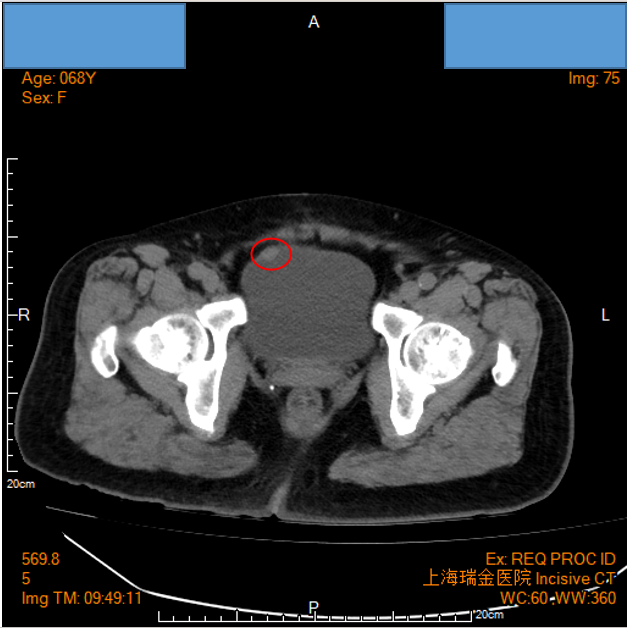

患者为一位68岁女性,因突发性右侧腰背部剧痛就诊。初步腹部CT平扫显示右侧输尿管结石伴随上段扩张及右肾积水。在症状缓解后进行的CTU检查中,意外发现膀胱前壁存在一处结节。

影像学检查提示:膀胱右前壁占位性病变

手术过程中,在膀胱右前壁观察到一个位于黏膜下的椭圆形肿物,基底较宽,尺寸约为1.5cm。